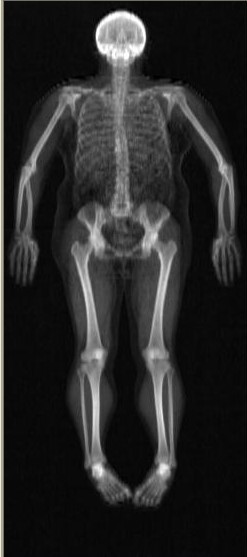

Depuis une dizaine d’années, je participe à une étude pancanadienne sur le vieillissement. Comme un cobaye, je me prête à toute sorte de questionnaires, mesures, imagerie médicales. Je trouve personnellement que c’est passionnant, et important de contribuer. Mais ça me rappelle bien sûr que je vieillis. L’illumination pour ce projet a commencé quand j’ai vu mon squelette de pied en cap. Oh ! c’est moi ! Sous moi! Pas juste un petit bout. Il me fallait faire quelques chose avec ça. J’ai commencé à imaginer des représentations, des supports, des techniques, des images, des couleurs… Mais le défi c’est de canaliser tout cela.